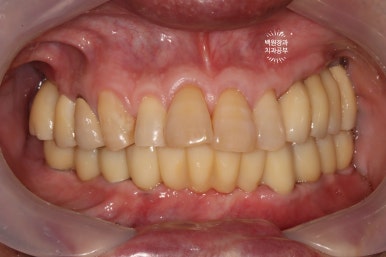

드디어 전체임플란트가 완성되었습니다!!

짜잔!!! 정말 비슷한 색상으로 제작이 잘 되어왔습니다.

최종 크라운을 연결하고나니 그렇게 깔끔할수가 없네요.

Before & After

치료 전 후 비교로 가장 명확히 볼 수 있는 사진이 치과용 파노라마 사진입니다.

엑스레이에서 보이진 않지만, 아래턱 전체틀니는 이제 사용하지 않아도 되시게 되었고,

만성 치주염으로 흔들리던 위턱의 임플란트들도 깔끔하게 임플란트로 대체되었습니다.

정면 사진입니다.

무면허업자에게 치료 받으셨던 어금니는 이제 하얀 지르코니아 크라운을 가진 임플란트로 대체되었습니다.

아래 틀니는 사라지고, 이젠 고정식의 임플란트로 바뀌었네요!

작은 충치들은 치아색의 레진으로 치료되어, 최종 치료결과는 아주 만족스러움 그 잡채!